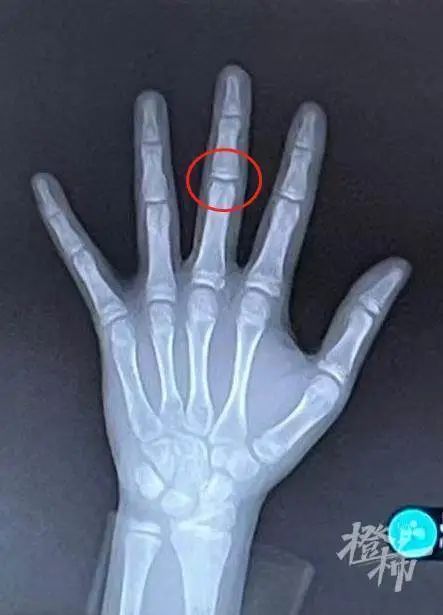

骨龄未闭合

骨龄已近闭合